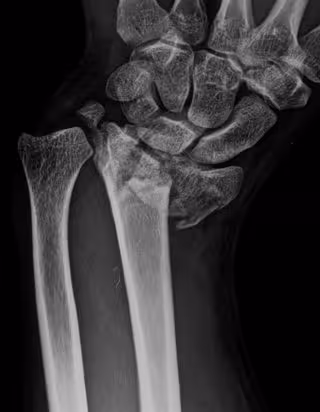

Fractura de radio

Fractura de radio - HOSPITAL LA LUZ - Archivo